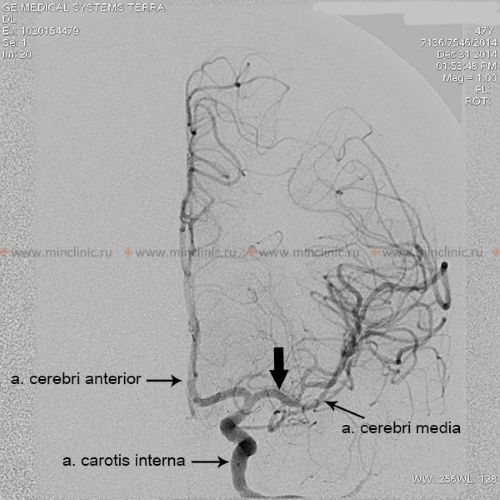

როდესაც გული ცალსახად იდენტიფიცირებულია, როგორც ემბოლიური წყარო, კვლევები მიუთითებენ თავის ტვინში განაწილების გარკვეულ პატერნზე. გულისმიერი ემბოლების დაახლოებით 80% მიდრეკილია გაიჭედოს ტვინის შუა არტერიის აუზში (რადგან ის იღებს საძილე არტერიის სისხლის ნაკადის ყველაზე დიდ ნაწილს), დაახლოებით 10-11% შეიძლება გადაადგილდეს ტვინის უკანა არტერიის აუზში (უკანა ცირკულაციის მეშვეობით), ხოლო დანარჩენი ნაწილდება ტვინის წინა არტერიის აუზში ან უშუალოდ ხერხემლის ან ბაზილარულ არტერიებში ან მათ ტოტებში [1, 2].

ნევროლოგიური დეფიციტების გარკვეული პატერნები მკაცრად მიუთითებს ცერებრული არტერიის ემბოლიაზე, როგორც გამომწვევ მიზეზზე [1, 2]. ტვინის შუა არტერიის (MCA) აუზში ემბოლიასთან დაკავშირებული სინდრომები ხშირად მოიცავს:

თუ ეჭვია ცერებრული არტერიის ემბოლიაზე, არტერიული ოკლუზიის ადგილმდებარეობის იდენტიფიცირება და ქვემოთმდებარე ტვინის ქსოვილის შეფასება კრიტიკულია მწვავე მკურნალობის (როგორიცაა თრომბექტომია) დასაგეგმად [16, 19]. არაინვაზიური სისხლძარღვოვანი ვიზუალიზაცია, როგორიცაა კტ ანგიოგრაფია (CTA) ან მრ ანგიოგრაფია (MRA), ჩვეულებრივ ტარდება გადაუდებლად [16]. კონვენციური კათეტერზე დაფუძნებული ცერებრული ანგიოგრაფია (ციფრული სუბტრაქციული ანგიოგრაფია - DSA) უზრუნველყოფს სისხლძარღვების უმაღლესი რეზოლუციის დეტალებს, მაგრამ არის ინვაზიური [14]. ის შეიძლება ჩატარდეს, თუ იგეგმება ენდოვასკულური მკურნალობა (თრომბექტომია) ან თუ არაინვაზიური ვიზუალიზაცია არასაკმარისად ინფორმატიულია [16, 19]. მნიშვნელოვანია აღინიშნოს, რომ რამდენიმე საათის ან დღის შემდეგ, ემბოლმა შეიძლება მიგრირება განიცადოს დისტალურად, ფრაგმენტაცია ან სპონტანური ლიზისი (დაშლა), რაც ნიშნავს, რომ მოგვიანებით ჩატარებულმა ანგიოგრაფიამ შეიძლება არ აჩვენოს თავდაპირველი ოკლუზია, რის გამოც ემბოლიური ინსულტის საბოლოო დიაგნოზი ზოგჯერ სავარაუდოა კლინიკური სურათისა და ინფარქტის პატერნის საფუძველზე [1]. სტანდარტული ინტრავენური კონტრასტის შეყვანა რუტინული კტ ან მრტ სკანირების დროს ზოგადად მოკლებულია იმ რეზოლუციას და დროით სიზუსტეს, რაც აუცილებელია სისხლძარღვებში მცირე ცერებრული ემბოლების უშუალო ვიზუალიზაციისთვის [14].